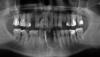

t348 Опубликовано 10 декабря, 2009 Поделиться Опубликовано 10 декабря, 2009 Добрый день. Мне 45 лет, зубы утеряны более года назад, нижние 2-ки сильно подвижные. Записался на консультацию к ортопеду. Подскажите, пожалуйста, возможные варианты протезирования - хочется подготовиться к пониманию того, что будут предлагать и оценить уровень клиники. Ссылка на комментарий

Андрей Опубликовано 10 декабря, 2009 Поделиться Опубликовано 10 декабря, 2009 Добрый день. Мне 45 лет, зубы утеряны более года назад, нижние 2-ки сильно подвижные. Записался на консультацию к ортопеду. Подскажите, пожалуйста, возможные варианты протезирования - хочется подготовиться к пониманию того, что будут предлагать и оценить уровень клиники.Вам надо кучу зубов удалять, кучу перелечивать и протезировать весь рот с использованием имплантатов - это по максимуму.Двойки тоже удалять и ставить имплантаты. Ссылка на комментарий

Нск Опубликовано 10 декабря, 2009 Поделиться Опубликовано 10 декабря, 2009 После удаления последнего "проблемного зуба";1. Съёмные протезы, доступный по стоимости вариант - "не отходя от станка".2. Наращивание кости - съёмные или несъёмные протезы, рациональный, более дорогой вариант . Ссылка на комментарий